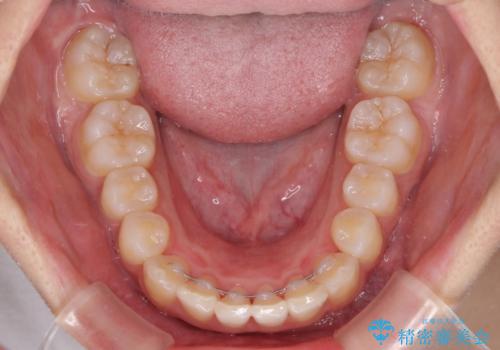

上顎左右前歯に矮小歯があるため、上顎の奥歯は下顎に対して相対的に前方に位置することになりました。

それでも奥歯の咬みにくさはなく、患者様には大変満足していただきました。